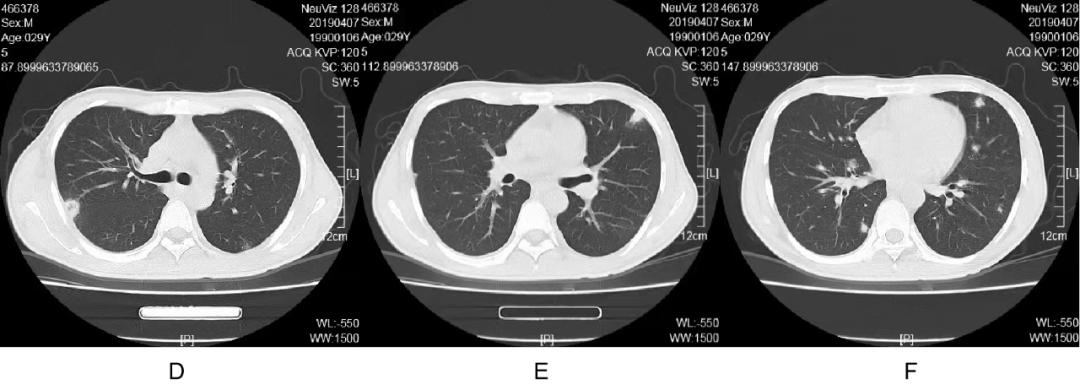

男,29 岁,既往有糖尿病病史,入院时无发热,胸部 CT 正常,中心静脉置管数日后出现发热、炎症因子增高。血培养提示:MRSA,胸部 CT 可见脓毒栓子,建议利奈唑胺治疗,但患者因经济原因拒绝,遂调整为万古霉素,次日热退,8 天后胸部 CT 复查,脓毒栓子出现明显增大。下面是发热后的 CT:

注:D~F:胸膜下脓毒栓子部分为楔形

8 天后改用利萘唑胺治疗,病人自诉比用万古霉素时身体舒服多了,因经济原因病人拒绝再次复查胸部 CT。

治疗 MRSA,如果单纯血流感染,宜选用万古霉素,因为其血液浓度高;如果是肺部感染,宜选用利奈唑胺,因为其在肺泡浓度高。 本例是医生对药物组织浓度不熟悉以及实际情况的局限。